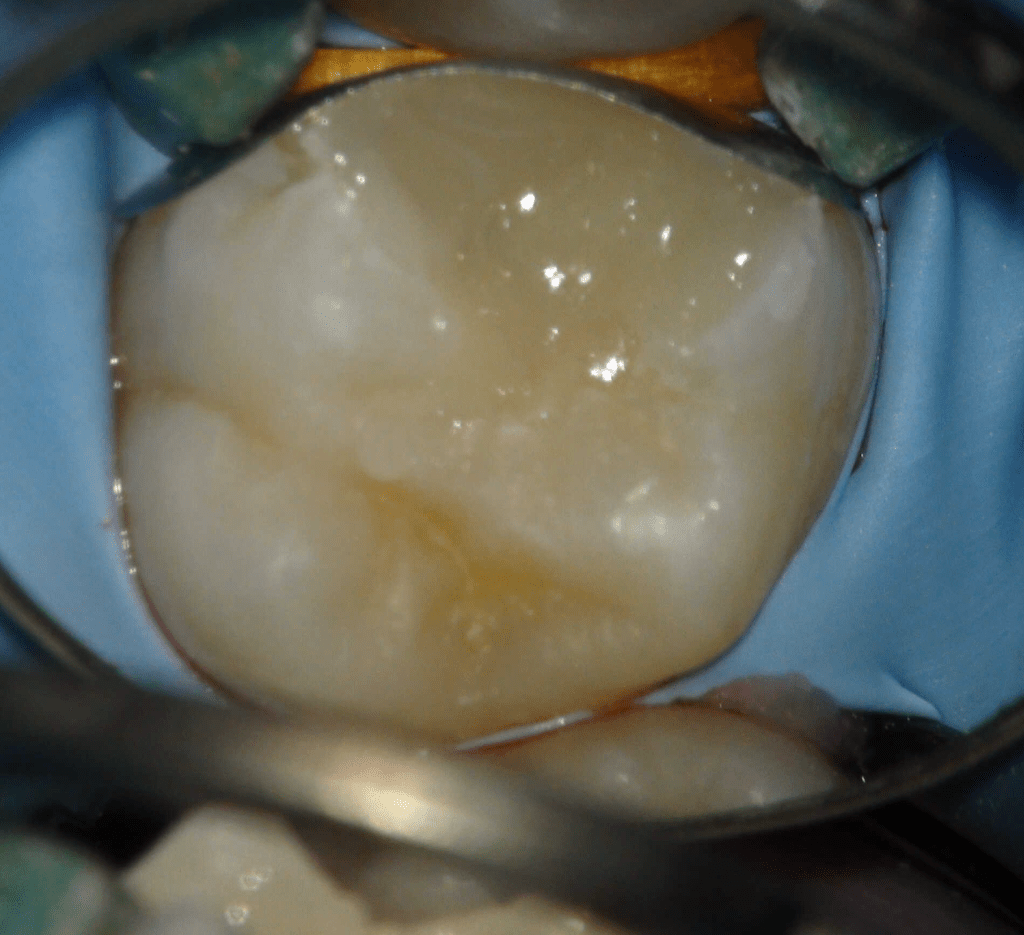

Pulpotomía biodentine + reco preendio